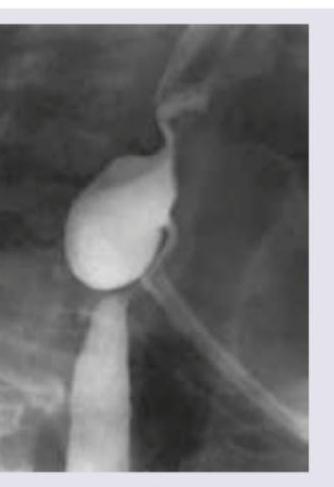

An 80-year-old female presents with complaints of difficulty swallowing and foul breath for 4 months. On auscultation, her lung fields have crepitations. A barium swallow finding is shown. What is your diagnosis?

Explanation: ***Zenker's diverticulum*** - The classic triad of **dysphagia**, **halitosis** (foul breath from food stagnation), and **pulmonary crepitations** (from aspiration) in an elderly patient strongly suggests Zenker's diverticulum. - Barium swallow typically shows a **posterior pharyngeal pouch** at **Killian's triangle** (between the thyropharyngeus and cricopharyngeus muscles). *Plummer-Vinson syndrome* - Characterized by **iron deficiency anemia**, **esophageal webs**, and **dysphagia** in middle-aged women, not elderly patients. - Associated with **koilonychia** (spoon-shaped nails) and **glossitis**, which are not mentioned in this case. *Schatzki's ring* - Presents with **intermittent dysphagia** to solids only, typically triggered by eating bread or meat ("steakhouse syndrome"). - Barium swallow shows a **thin circumferential ring** at the gastroesophageal junction, not a posterior pouch. *Corkscrew esophagus* - Associated with **diffuse esophageal spasm** causing severe **chest pain** and dysphagia to both liquids and solids. - Barium swallow shows **tertiary contractions** creating a corkscrew appearance, not a diverticular pouch.